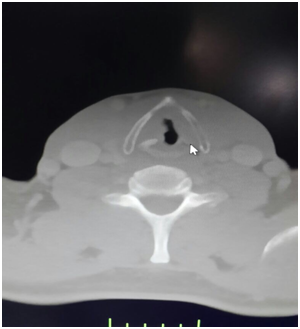

1 year ago, a 52year old male patient was diagnosed T3 glottic cancer and he did not consent to operation and he was underwent radiotherapy of the neck region due to lymph node metastasis (Figure 1). About four months after radiotherapy, halithosis and difficulty in breathing occurred and ear nose throat department planned tracheostomy (Figure 2). Patient had cachectic appearance and anaerobic odor was present. Preoperative SpO2: 82%, blood presure: 140/80 mm/Hg and heart rate: 110 beats/min. In anesthesia induction, 2mg/kg propofol, 0.6mg/kg rocuronium (Esmeron, Schering Plough, Turkey) and 1.5mcg/kg fentanyl (Talinat, Vem, Turkey) were administered. After oxygen saturation value was increased from 82% to 98% with mask ventilation, suspension blade was placed. In endoscopy, it was observed that right side of trachea was necrotic in subglottic region and necrosis extended towards strap muscles (Figure 3). While necrotic areas are cleaned, desaturation was prevented by 100% O2 18 lt/min. flow insufflations. During skin incision for tracheostomy, intubation was made carefully with endoscopy. At the level of 2nd and 3rd rings of trachea, necrotic areas at right lateral were excised and cannula was placed. In the meantime biopsy was taken and tumor didn’t occur in the biopsy result. Patient was awakened without any complications and transferred to clinic.